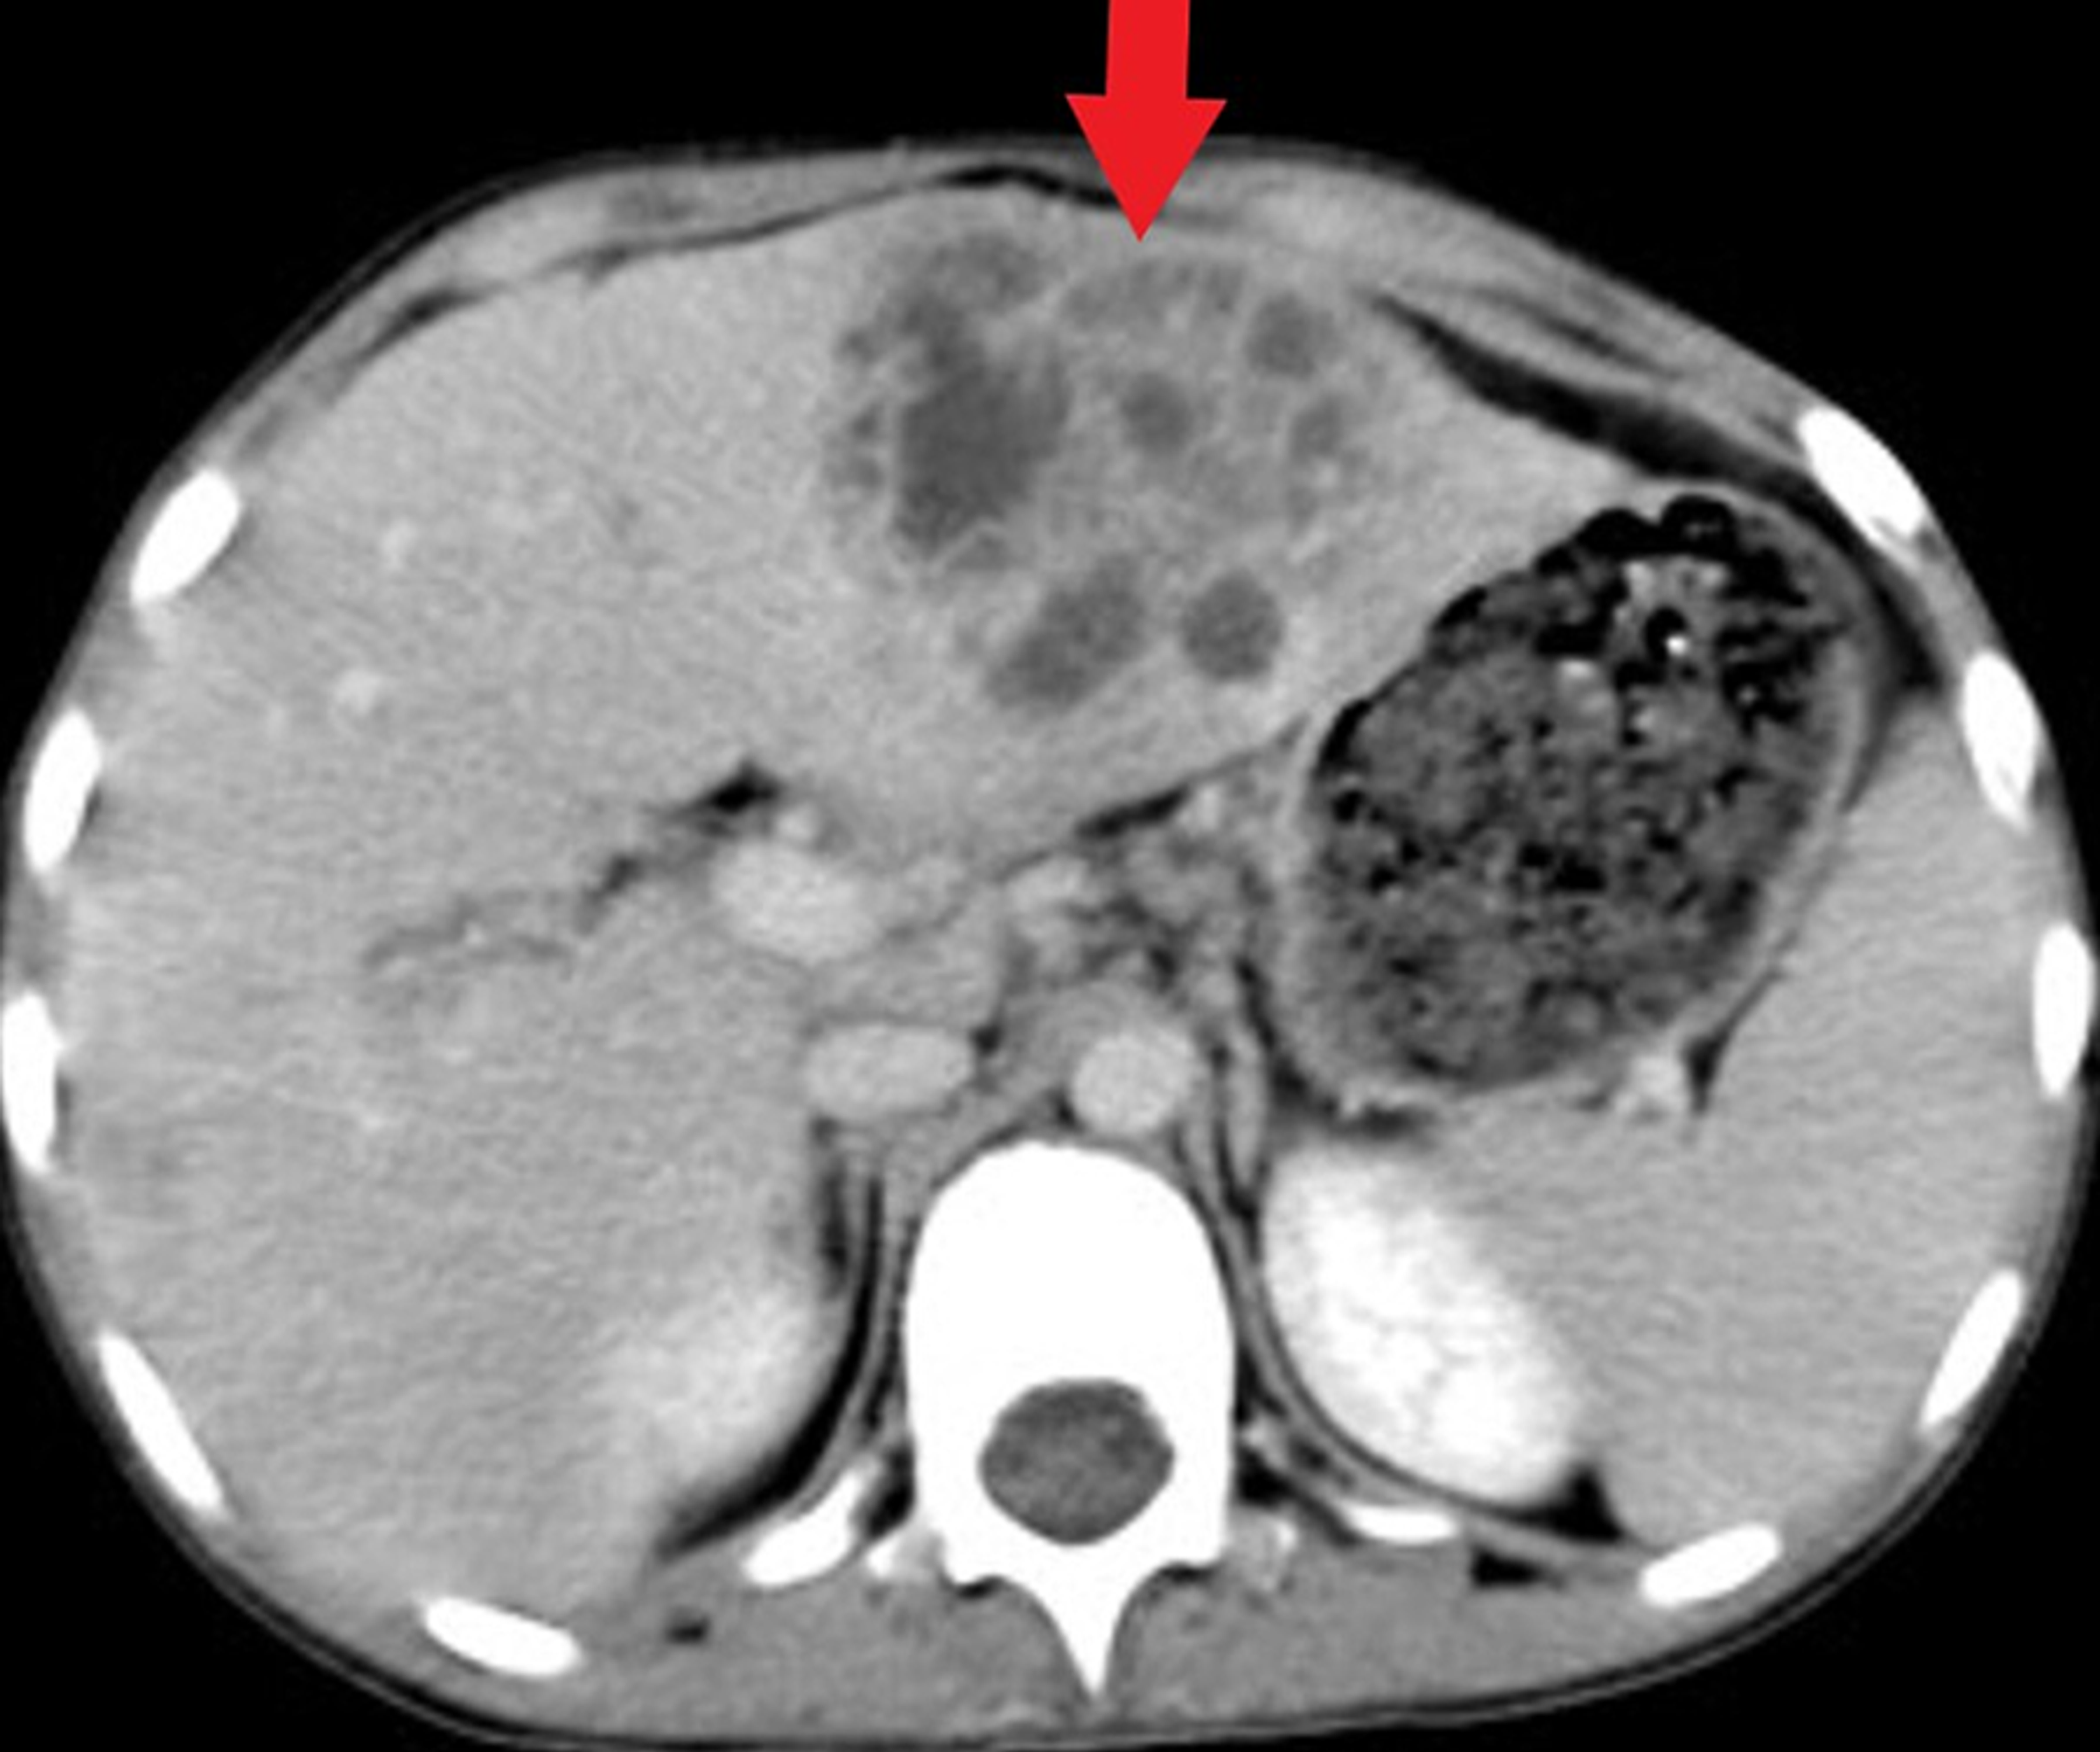

From www.wikidoc.org

Amoebic liver abscess CT wikidoc Liver Abscess Wiki Associated with biliary tract obstruction (most common), cholangitis, diverticulitis, pancreatic abscess, appendicitis and inflammatory bowel disease. Pyogenic liver abscesses usually develops in the context of biliary disease, portal pyemia of various causes, through arterial. Liver abscess is a localized infection in the liver parenchyma that may be bacterial, fungal, or parasitic in origin. Liver Abscess Wiki.